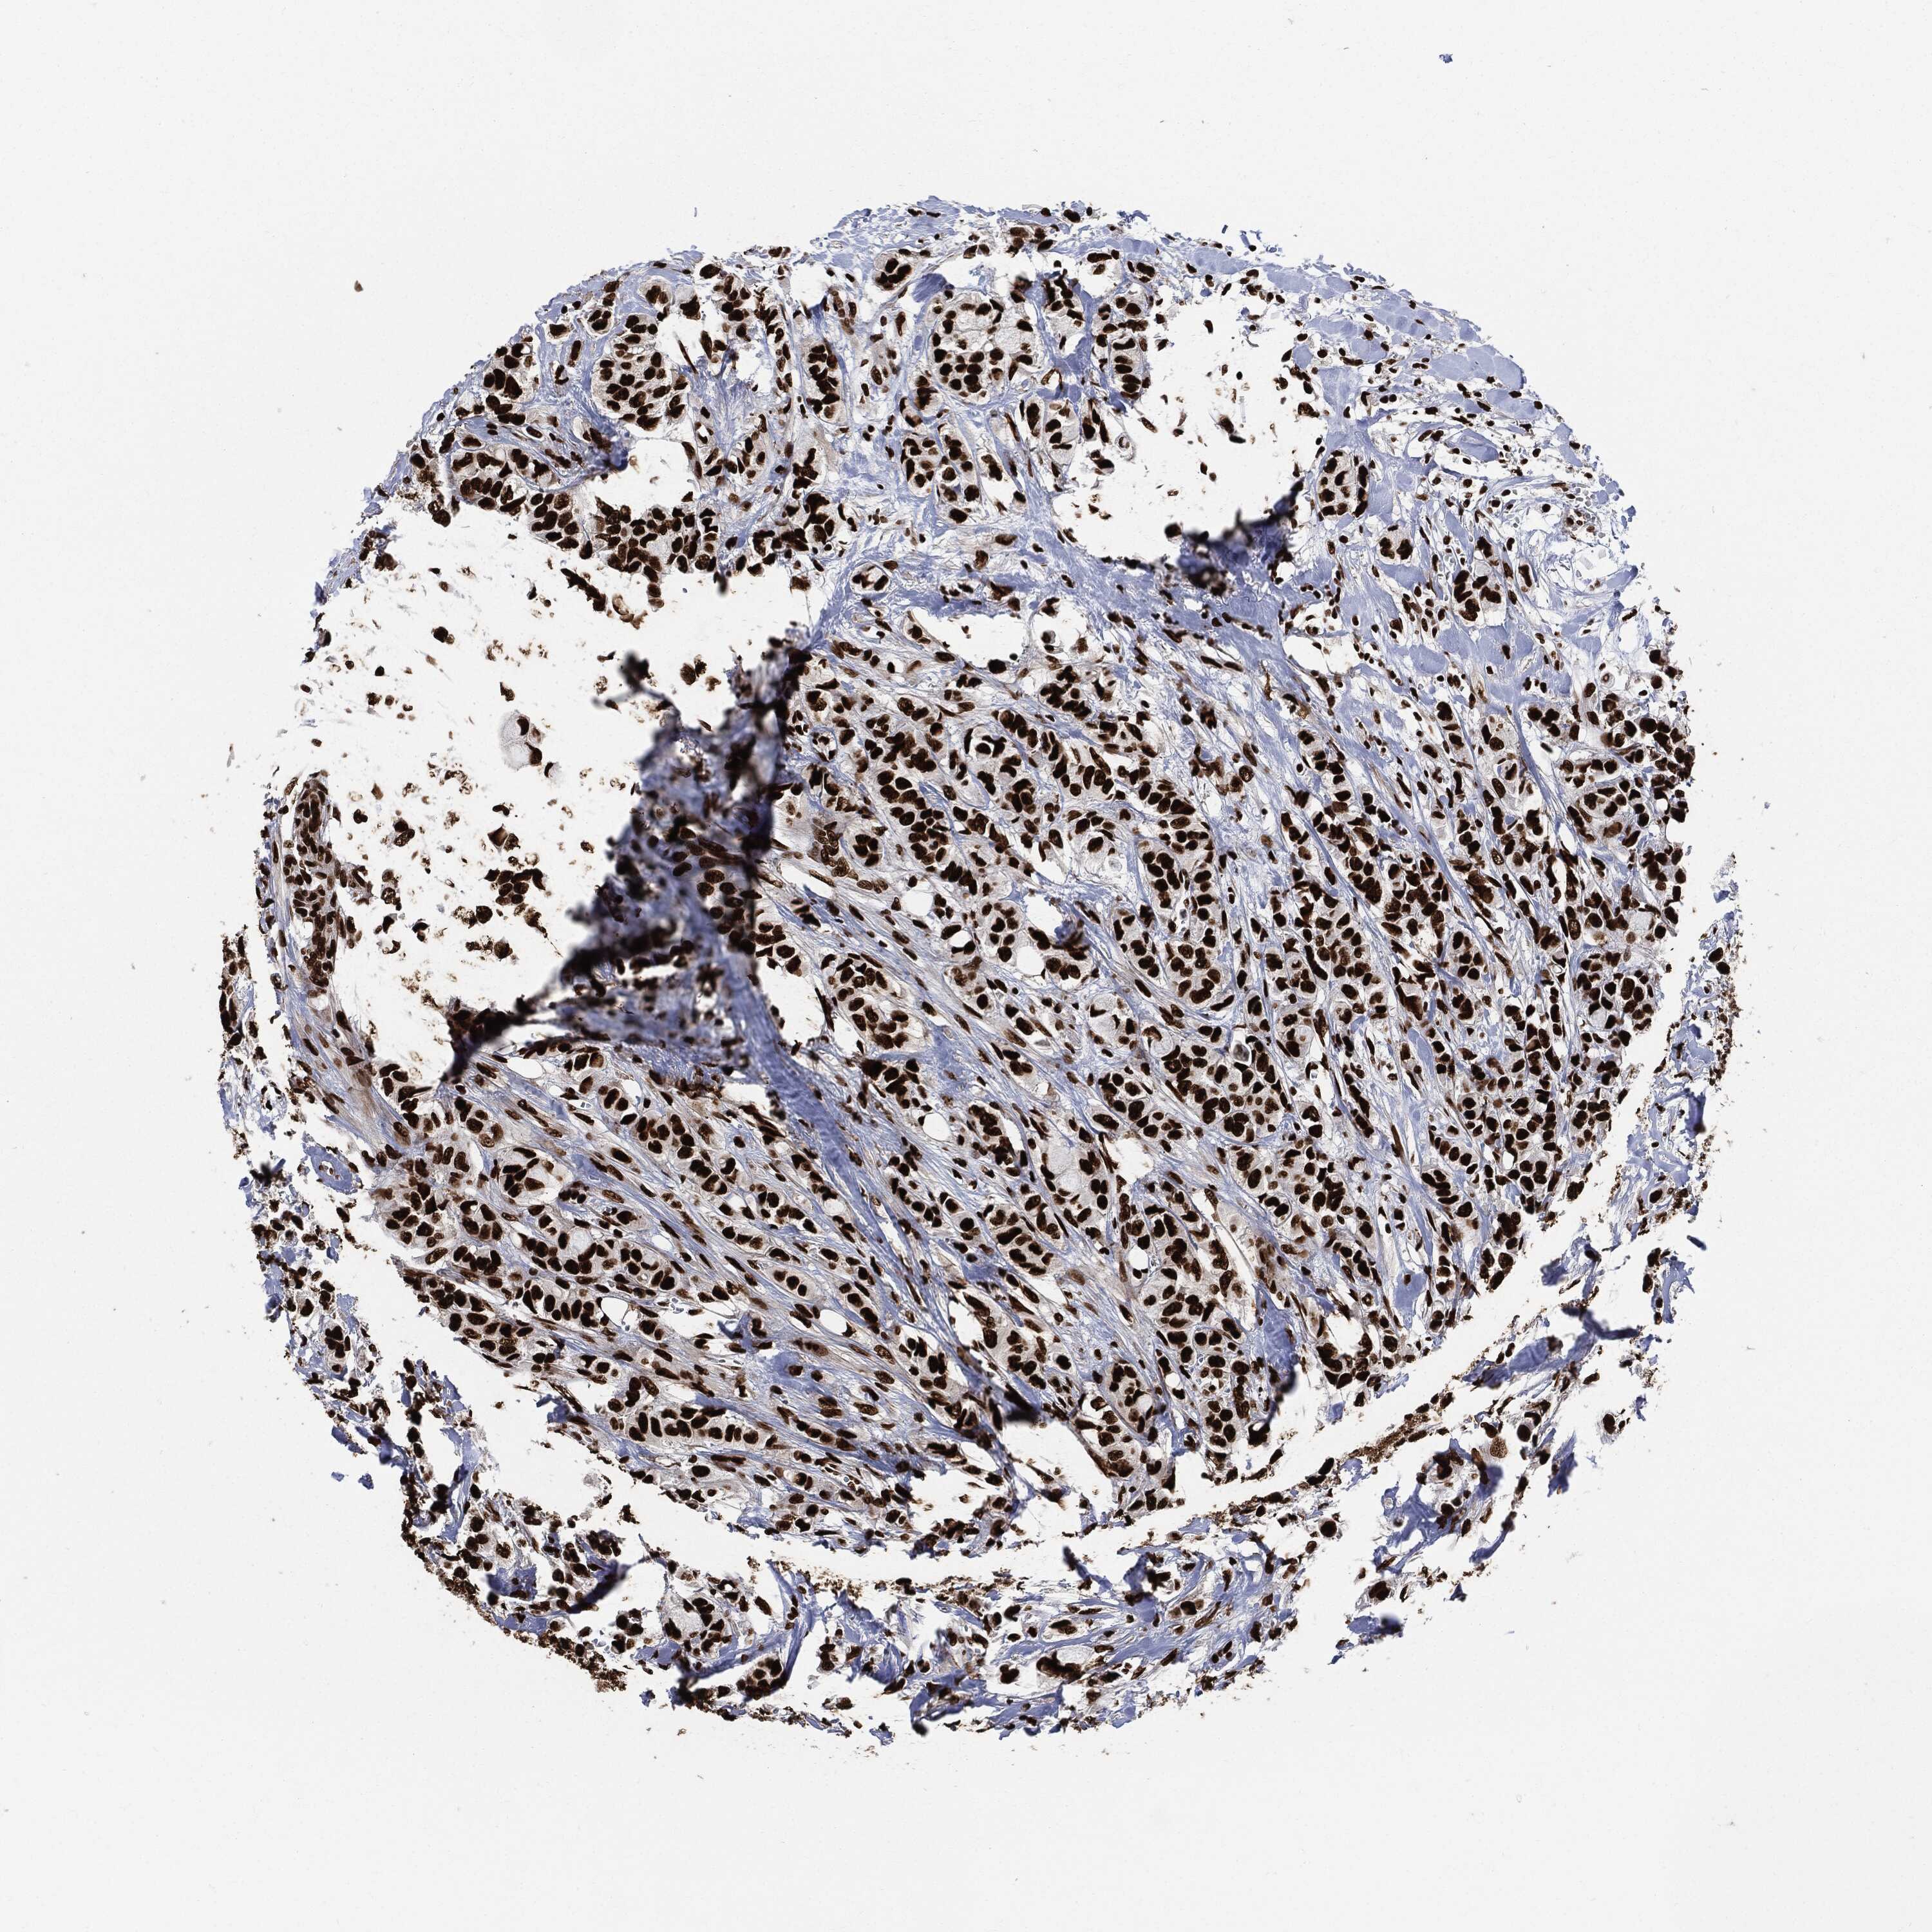

CANCER BREAST CANCER Show tissue menu

BRCA TCGA BRCA VALIDATION PROTEIN EXPRESSION

ANTIBODIES

AND

VALIDATION